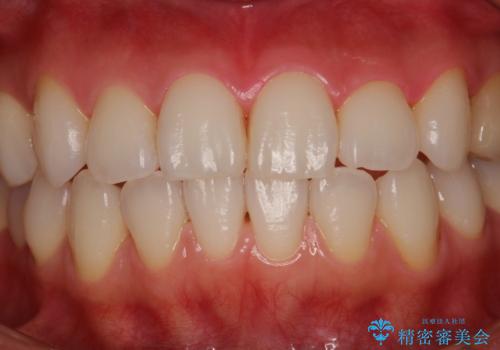

- 久しぶりの来院で歯磨きチェックとクリーニング希望とのことでした。染め出しとPMTC30分コースを行いました。

一見きれいに見える歯でも、染め出し(歯垢染色液)を使うとこのように歯と歯茎の境目や、歯と歯の間などに磨き残しがあることがわかります。歯磨きには、いつも気をつけているから磨き残しはナシと思っていても、実際完璧に磨ききることはなかなか難しいです。歯科医院にて、専門の機械で定期的なPMTCを行うことが大切です。